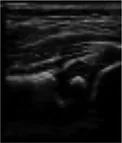

In this study, the GE LOGIQ-E9 ultrasonic diagnostic instrument (America) and 9l linear probe with a frequency range of 5.0–9.0 MHz were employed for imaging of the hip joint. The ultrasound coronal plane of Graf’s method was chosen as the standard imaging technique for this purpose. The imaging procedures were conducted by experienced senior physicians who possess the necessary expertise and technical skills in ultrasound imaging. In the standard imaging, four markers were identified, namely the iliac bone, bony rim point, lower iliac limb point, and glenoid labrum, as illustrated in Figure 2. These markers were selected based on their ability to provide accurate and reliable measurements of the hip joint. The utilization of a standardized imaging protocol and the identification of these markers allowed for consistent and reproducible imaging of the hip joint, ensuring the validity and reliability of the data obtained in this study.

FIGURE 2

www.frontiersin.org

Figure 2. Measurement of the neutral coronal plane of the hip joint using the graf method. (A) Iliac bone, (B) bony rim point, (C) lower iliac limb point, (D) glenoid labrum.